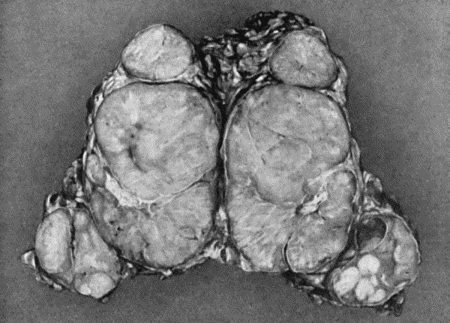

| 78. | Mass of Tuberculous Glands removed from Axilla | 333 |

| 79. | Tuberculous Axillary Glands | 335 |